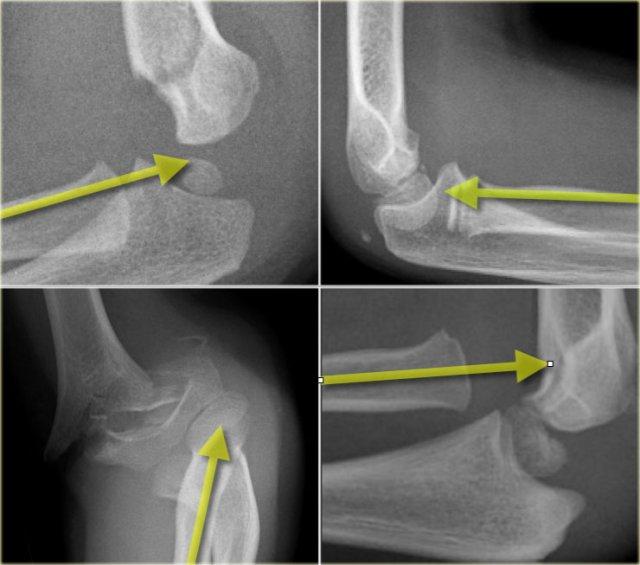

Có hai đường quan trọng giúp chẩn đoán trật khớp và gãy xương.

Đó là đường Quay-Chỏm (Radiocapitellar) và đường Cánh tay trước (Anterior humeral).

Đường quay-chỏm

Một đường kẻ qua trung tâm cổ xương quay phải đi qua trung tâm của chỏm con, bất kể tư thế của bệnh nhân như thế nào, vì xương quay khớp với chỏm con (hình minh họa).

Trong trường hợp trật xương quay, đường này sẽ không đi qua trung tâm của chỏm con.

Ở bên trái, chúng ta thấy rằng đường quay-chỏm đi qua trung tâm của chỏm con trên mọi phim X-quang, mặc dù C và D không ở tư thế chuẩn.

Lưu ý gãy xương trên lồi cầu ở hình B.

Bên trái là các ví dụ khác về đường thẳng quay-chỏm.

Hình ảnh phía dưới bên phải cho thấy sự trật khớp rõ ràng của xương quay.